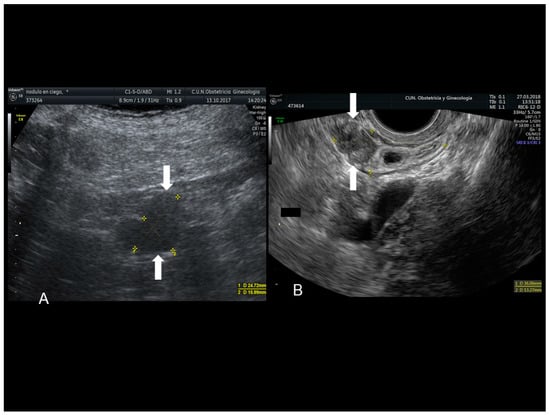

Figure 12. Sonographic features of an endometriotic nodule of cecum (see white arrow) (A) and appendix (see white arrow) (B).

3.1. Endometriosis of the Appendix

The appendix is also an unusual site of extra-pelvic endometriosis. Endometriotic lesions affecting this area may be asymptomatic or may provoke acute appendicitis, melena, ruptured bowel or obstructed bowel from intussusception. Appendiceal endometriosis has a typical histopathological appearance: the mucosa is always left unscathed while the endometrial glands, stroma and hemorrhagic foci are gathered in the muscular and seromuscular layers [24]. Appendiceal endometriosis may have similarities with the clinical presentation of diverticular disease, colorectal cancer, inflammatory bowel disease, carcinoid tumors, benign intramural neoplasms, occult intra-abdominal metastases, mesenteric neoplasms and pelvic abscesses [25]. In ultrasonography appendiceal endometriosis is characterized by a solid lesion in the wall of small bowel, usually well defined (Figure 12, Figure 13, Figure 14 and Figure 15).